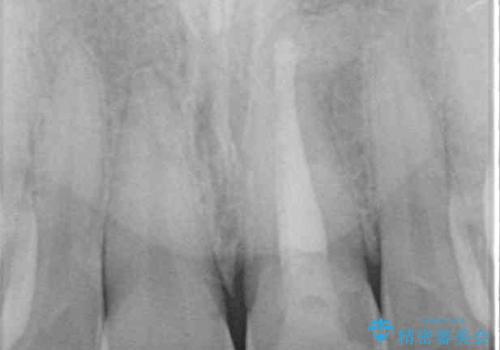

- 以前ぶつけて神経を取り除いてから、徐々に変色してきた前歯が気になるとのことで来院された患者様です。

神経を取り除いた歯の変色はホワイトニングでは十分に改善できないため、オールセラミッククラウンにて補綴治療を行うこととしました。